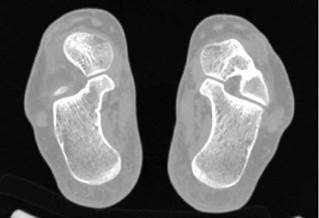

Our study involved the processing of bone CT images, so as to identify the region of bone cancer and perform a 3D evaluation. Axial raw CT images containing healthy and bone tumors are presented in Figures 2 and 3.